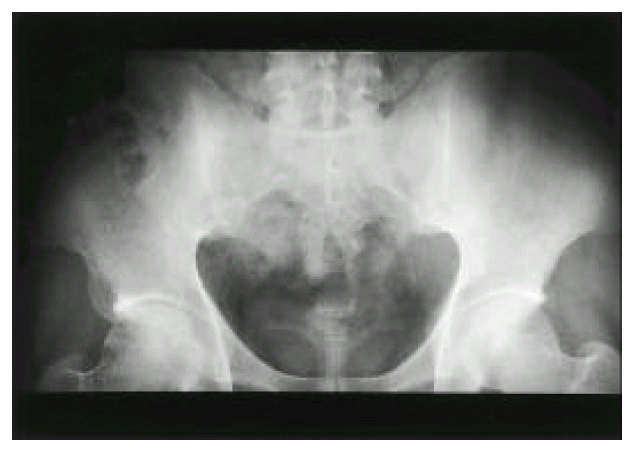

Physical examination revealed multiple aphthous ulcers on the buccal mucosa, papulopustular eruptions on the anterior chest, and scrotal ulcer. There were tenderness and swelling on the right knee. The chest expansion was 5 cm and the modified Shobber test was 15 cm. The pathergy test was negative. Hematological and biochemical tests were as follows: WBC 9200/mm3, hematocrit 40.1%, platelet 321000/mm3, total protein 7.2 g/dl, albumin 4.4 g/dl, AST 26 IU/L, ALT 35 IU/L, creatine kinase 76 IU/L. Erythrocyte sedimentation rate was 30 mm/hr and C-reactive protein was negative. Urinalysis and coagulation tests were normal. Rheumatoid factor, antinuclear antibody and antineutrophil cytoplasmic antibody were negative. Both HLA-B27 and B51 antigens were positive. Bilateral SI (right: grade 4, left: grade 3) was noted on plain pelvis radiograph (Figure 1) and T2-weighted magnetic resonance imaging (Figure 2).

Fig. 1.

Plain pelvis radiograph shows the obliteration of joint space in both sacroiliac joints (right>left) and the juxta-articular bony sclerosis.